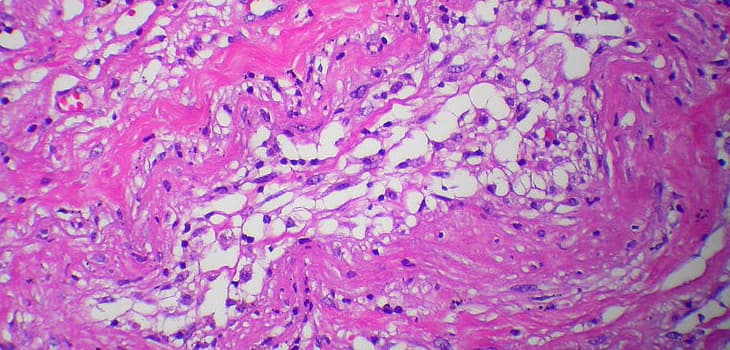

Approved by the FDA and awarded “Best New Technology in Sports Medicine,” Lipogems orthopedics is now an essential treatment for professional athletes and advanced sports enthusiasts. Thanks to the use of autologous adipose tissue, Lipogems naturally regenerates injuries to the knee, shoulder, and hip, as well as chondropathies and tendinopathies. It promotes deep healing, reduces pain, and optimizes recovery. Increasingly adopted by leading sports medical teams, Lipogems is used both to prevent joint degeneration and to support post-operative recovery, reducing the risk of recurrence and improving long-term functional outcomes. In a field where recovery time is critical, Lipogems stands out as a natural, regenerative, and scientifically validated solution. It is also available in Milan at Image Regenerative Clinic, with documented case studies and positive feedback from high-level athletes. Sports medicine has already changed direction: today, we no longer replace—we regenerate.

Lipogems Sport is the advanced solution for treating sports injuries that are complex and resistant to traditional therapies. Tendinopathies: tennis elbow, Achilles, patellar and rotator cuff tendinitis for complete functional recovery. Cartilage lesions: knee, hip, ankle chondropathies to avoid destructive interventions. Chronic sprains: ankle and knee instability with persistent pain and functional limitation. Muscle injuries: recurrent strains and tears that compromise athletic performance. Overuse syndrome: training overload with chronic joint pain. Early arthritis: joint degeneration in young athletes to preserve sports career.